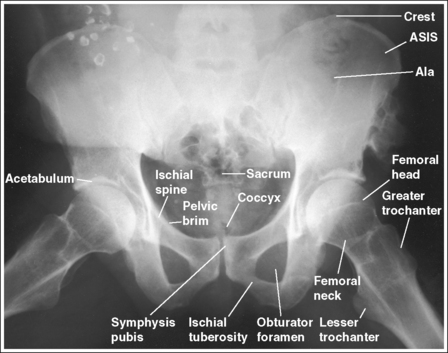

See Figures 7-21 and 7-22 and Box 7-5.

• Regarding the male and female pelves. Be aware of the bony architectural differences that exist between the male and female pelves (Table 7-2). These differences are the result of the need for the female pelvis to accommodate fetal growth during pregnancy and fetal passage during delivery.

The pelvis demonstrates an AP projection. The ischial spines are aligned with the pelvic brim, the sacrum and coccyx are aligned with the symphysis pubis, and the ilia and obturator foramina are open and uniform in size and shape.

• An AP projection of the pelvis is accomplished by placing the patient supine on the imaging table, with the legs extended and the arms drawn away from the pelvic area (Figure 7-23). To ensure that the pelvis is not rotated, judge the distance from the ASIS to the imaging table on each side. The distances should be equal.